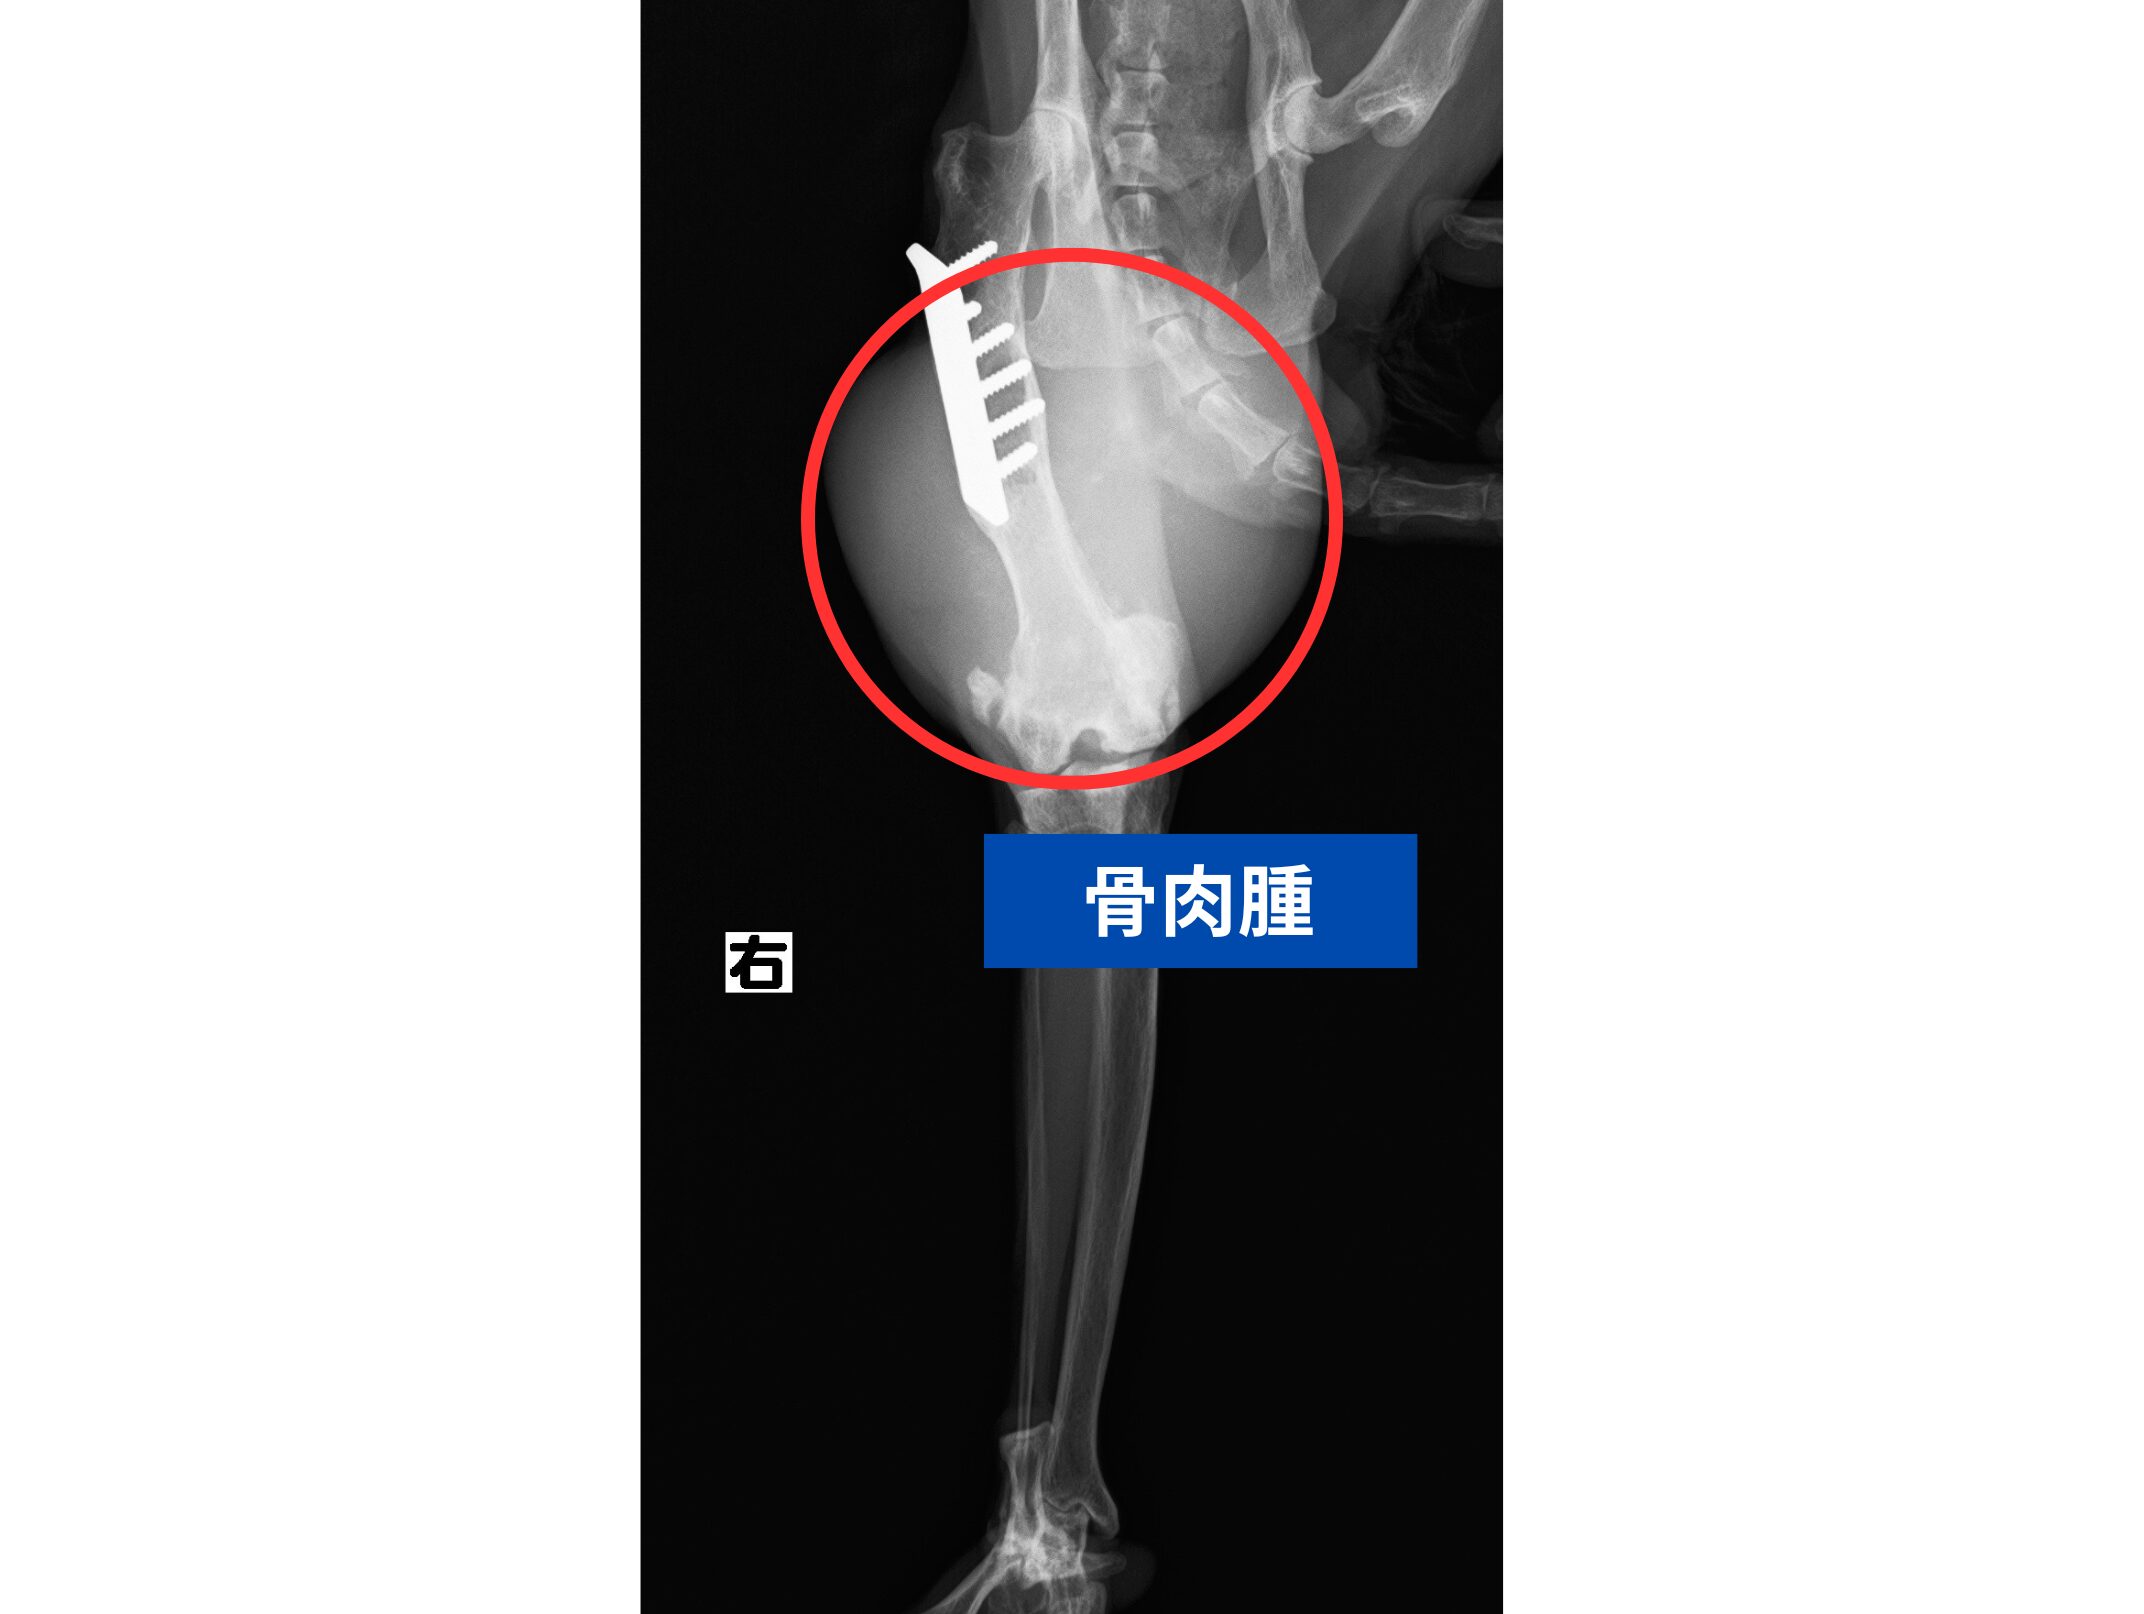

当院でレントゲン検査を実施したところ、左後肢の骨に異常な骨の破壊像が確認されました。

過去に他院で手術の際に入れられたプレート周囲から腫瘍が発生している可能性が疑われました。

確定診断のためパンチ生検を行い、病理組織学的検査の結果、骨肉腫と診断されました。

次の画像が検査時のレントゲン画像です。